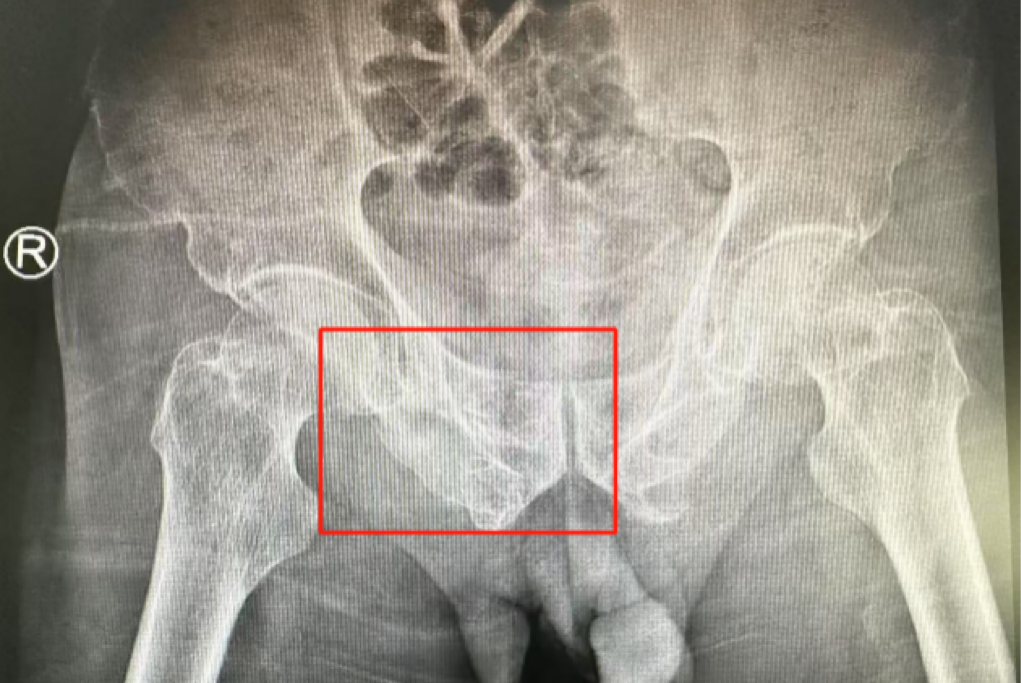

術前影像學顯示,患者的左側骶骨骨折,右側恥骨骨折、髂骨骨折,骨盆骨折分型為C型,老年脆性骨盆骨折分型為IV型,是極度不穩定型的前環骨折和雙側后環骨折。所幸沒有明顯的骨盆出血或內臟損傷的表現。

術后第二天,醫生團隊復查X片顯示螺釘植入位置非常滿意,骨折基本達到穩定復位,同時,復查的全血細胞計數中,血紅蛋白指數為102g/L。術后第三天,在智能骨科病房護理團隊及康復師的指導和護理下,王大爺可以坐立在床上。術后第四天,王大爺迎來了出院日,“得虧有了這么先進的醫療技術,讓我還能下地行走,謝謝你們!”

螺釘植入位置非常滿意